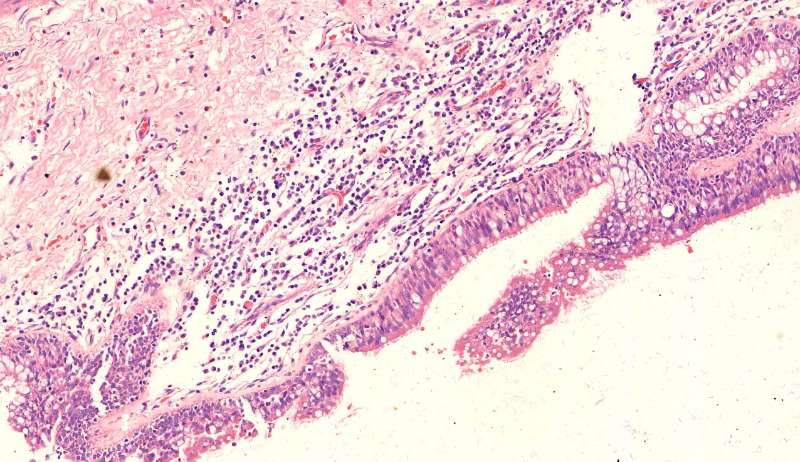

蓝色圈圈是菌丝团?红色箭头是淋巴细胞?这是空腔边缘吗?王:是的,红箭头也可能是中性粒细胞。 红箭是支气管粘膜有炎症。

这里的菌丝形态清楚,下图小圆空的结构挺多,我理解为管状菌丝的断面

支气管扩张都有平滑肌增生吧?王:一般会有 王老师 ,这些是单纯HE染色还是有特殊染色?王:HE